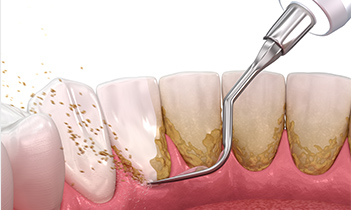

スケーリング

スケーラーと呼ばれる専用の器具を使用して行う、歯周病治療の一種です。歯に付着した歯石や歯垢は歯周病など歯科疾患の原因となるため、スケーリングで徹底的に除去していきます。歯周病予防はもちろん、口臭対策にもなります。

SRP

Scaling and Root Planingの略であり、基本的な歯周病治療の方法です。スケーリングで歯の表面に付着した歯石を取り除き、ルートプレーニングで歯周ポケットの深い部分にある歯石も除去します。歯面を滑らかにして、歯石の再付着も防ぎます。